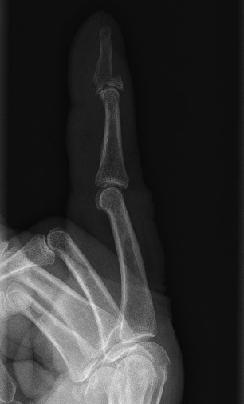

Lesões nos dedos, principalmente das mãos, são bastante frequentes durante a realização das atividades diárias, atividades esportivas, acidentes de trabalho ou quedas. Uma fratura no dedo pode levar tempo a curar, dependendo da localização e gravidade da fratura, por isso é fundamental identificá-la o mais rápido possível para minimizar a situação.

O mesmo acontece se você quebrar um dedo da mão, você vai sentir uma dor aguda e pode até ocorrer uma deformação do osso ou da articulação, que se conhece como luxação. E, muitas vezes consegue-se dobrar o dedo à mesma, apesar de estar quebrado.

Se o osso perfurou a pele, deve procurar ajuda médica de imediato pois muito provavelmente você tem o dedo quebrado. Além disso, se você tocar no dedo e sentir seu osso se movendo, este também pode ser um sinal de que o seu dedo está quebrado.

Perante a presença destes sinais, você deve procurar atenção médica para que lhe realizem uma radiografia e diagnostiquem o dedo quebrado. O tratamento vai depender do seu tipo de fratura. Caso a fratura seja simples, o médico irá colocar-lhe uma tala no dedo. Se for uma situação mais complexa, pode ser necessário a opinião de um ortopedista e a realização de uma cirurgia.